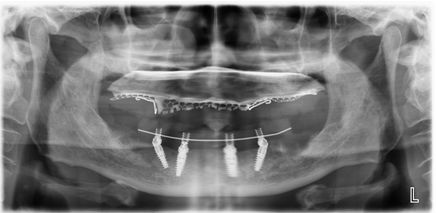

All-on-4全/半口種植技術(shù)突破傳統(tǒng)種植牙技術(shù),只需種入4顆(全口8顆)種植體,就可以恢復(fù)全/半口牙的咀嚼功能,在患者口腔狀態(tài)符合的條件下,可以實(shí)現(xiàn)當(dāng)天種牙,當(dāng)天戴牙冠吃東西。

2、單頜植入4個植體,遠(yuǎn)中兩個傾斜,上頜避開上頜竇前壁,下頜避開頦孔和下頜神經(jīng)。